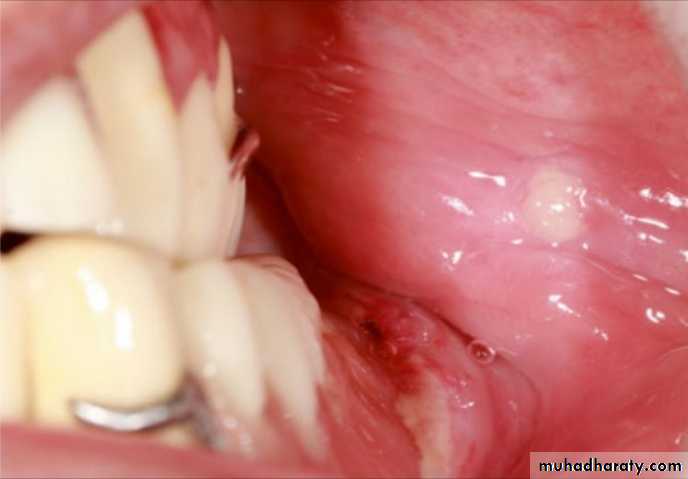

Tissue trauma reveals as increased redness or translucency in the oral mucosa. Increased redness is the symptom of the ulcerations, and a translucency may occur just before ulceration exists.

Post insertion problems

Overextension of the denture bases and the pressures on the fragile tissues such as incisive papilla or occlusal prematurities are the main causes of these ulcerations. Ulcerations due to tissue trauma develop generally at the initial recall appointments and can be solved easily by relieving the denture base parts touching the pain area. In case of overextension, ill-fitting RPDs, or acrylic irregularities, the areas can be identified by the aid of an indelible pencil or pressure- indicating paste. An ulceration due to tissue trauma caused by

the overextension of the lingual border of an RPD